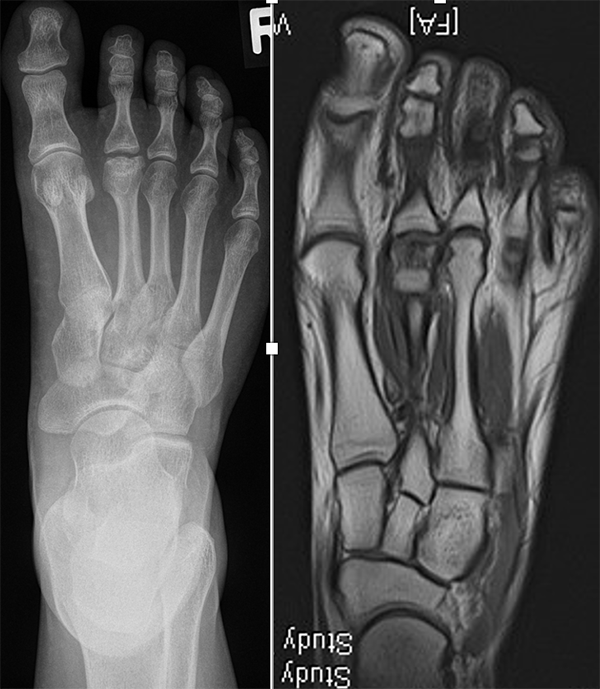

Zusätzlich schränken Wachstumsfugen die Wahl der Osteosynthese ein. Eine die Fuge kreuzende Osteosynthese ist ausschließlich mit Kirschner-Drähten möglich (Abb. 3).

Abb. 3 a-j: Beispiel einer Calcaneusverschiebeosteotomie mit offenen Wachstumsfugen und der entsprechenden Osteosynthese mit Kirschner Drähten. Lokalisation der Osteotomie (a), Lage der Fräse (b-d), Drahtlage mehrere Ansichten (e-h), Heilung der Osteotomie 4 Wochen postoperativ und Entfernung der Drähte (i-j).

Calcaneus-Osteotomie

Die minimalinvasive Calcaneusverschiebeosteotomie bietet eindeutige Vorteile gegenüber dem offenen Verfahren, sodass wir bei Kindern und Jugendlichen nahezu keine offene Verschiebeosteotomie mehr durchführen. Am Calcaneus liegt die offene Wachstumsfuge dorsal. Bei der Durchführung müssen Schenkel der V-förmigen Osteotomie daher etwas steiler angelegt werden, in einem stumpfen Winkel (siehe Abb. 3 a-j). Für die Osteotomie liegen unsere Patienten auf dem Rücken und der BV wird für die exakte Seitaufnahme eingestellt. Der Fuß lagert auf einem hohen OP-Kissen und die Osteotomie kann bequem mit einem langen Kirschner-Draht und einem sterilen Stift angezeichnet werden (Abb. 15).